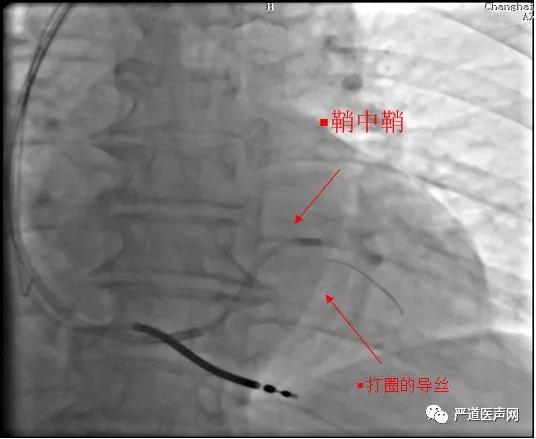

鞘中鞘造影确认靶血管

鞘中鞘的优势:

•头端柔软,提供支撑力,更容易帮助塑形导丝进入有成角的分支。

•直接造影,明确靶静脉。

鞘中鞘技术的应用

在美敦力的Attain Select TM+SureValveTM6248VI-130(鞘中鞘)引导下,Sion导丝顺利通过靶静脉第一个夹角,但是在继续推进导丝的时候却发现导丝打圈难以前进。

•左室电极植入是最关键技术。本例左室电极植入的难点是靶血管与主支血管成角大,而且靶血管中段扭曲,普通PTCA导丝无法进入靶血管远端

•运用鞘中鞘技术,很好地解决了靶血管与主支血管成角大问题,但依然无法将电极通过中段扭曲处